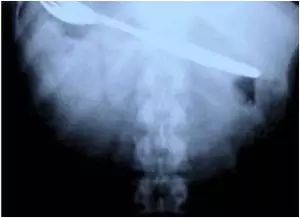

14.在佛罗里达的小狗胃里发现了一个13英寸的刀片,在动手术除去之前,至少已经停留了四天。

在佛罗里达的小狗胃里发现了一个13英寸的刀片,在动手术除去之前,至少已经停留了四天。